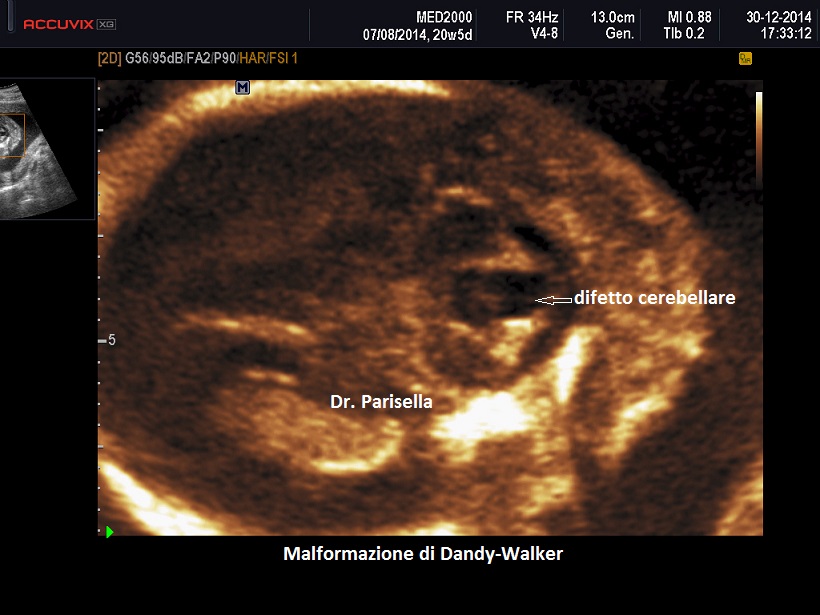

La diagnosi differenziale deve essere posta principalmente con la sindrome di Dandy-Walker: in tal caso è dirimente la presenza nella sindrome di Joubert del "segno del molare" e la familiarità.